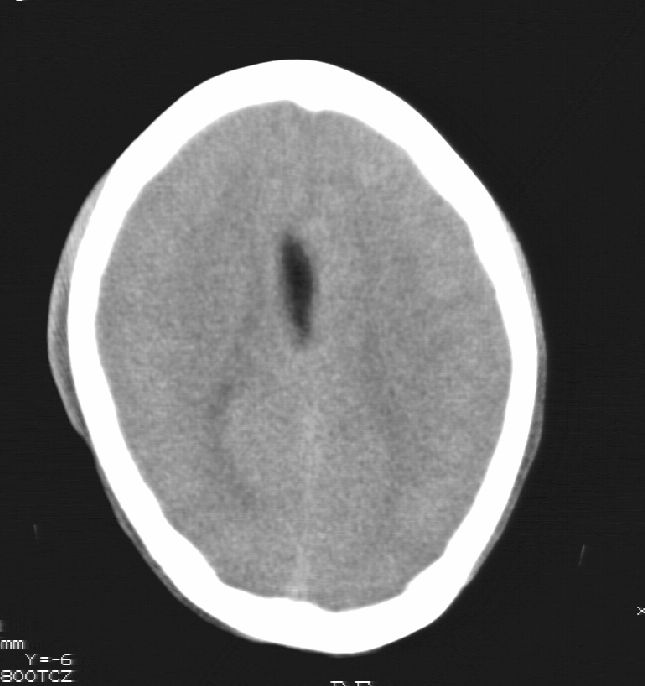

标题: CT25322:脑内发现混杂密度影

患者男,22岁,因外伤入院,低密度影ct值约-120hu。

胼胝体发育不全合并 透明隔缺如 、脂肪瘤。

胼胝体发育不全合并脂肪瘤;建议必要时行mri检查。

脑水肿,头皮下血肿,胼胝体发育不全、合并脂肪瘤及钙化;建议必要时行mri检查。

胼胝体发育不全、合并脂肪瘤及钙化。